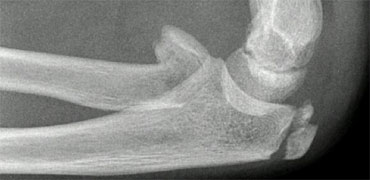

Then continue reading.

The radiocapitellar line ends above the capitellum.

This means that the radius is dislocated.

Did you also notice the olecranon fracture?

Whenever the radius is fractured or dislocated, always study the ulna carefully.